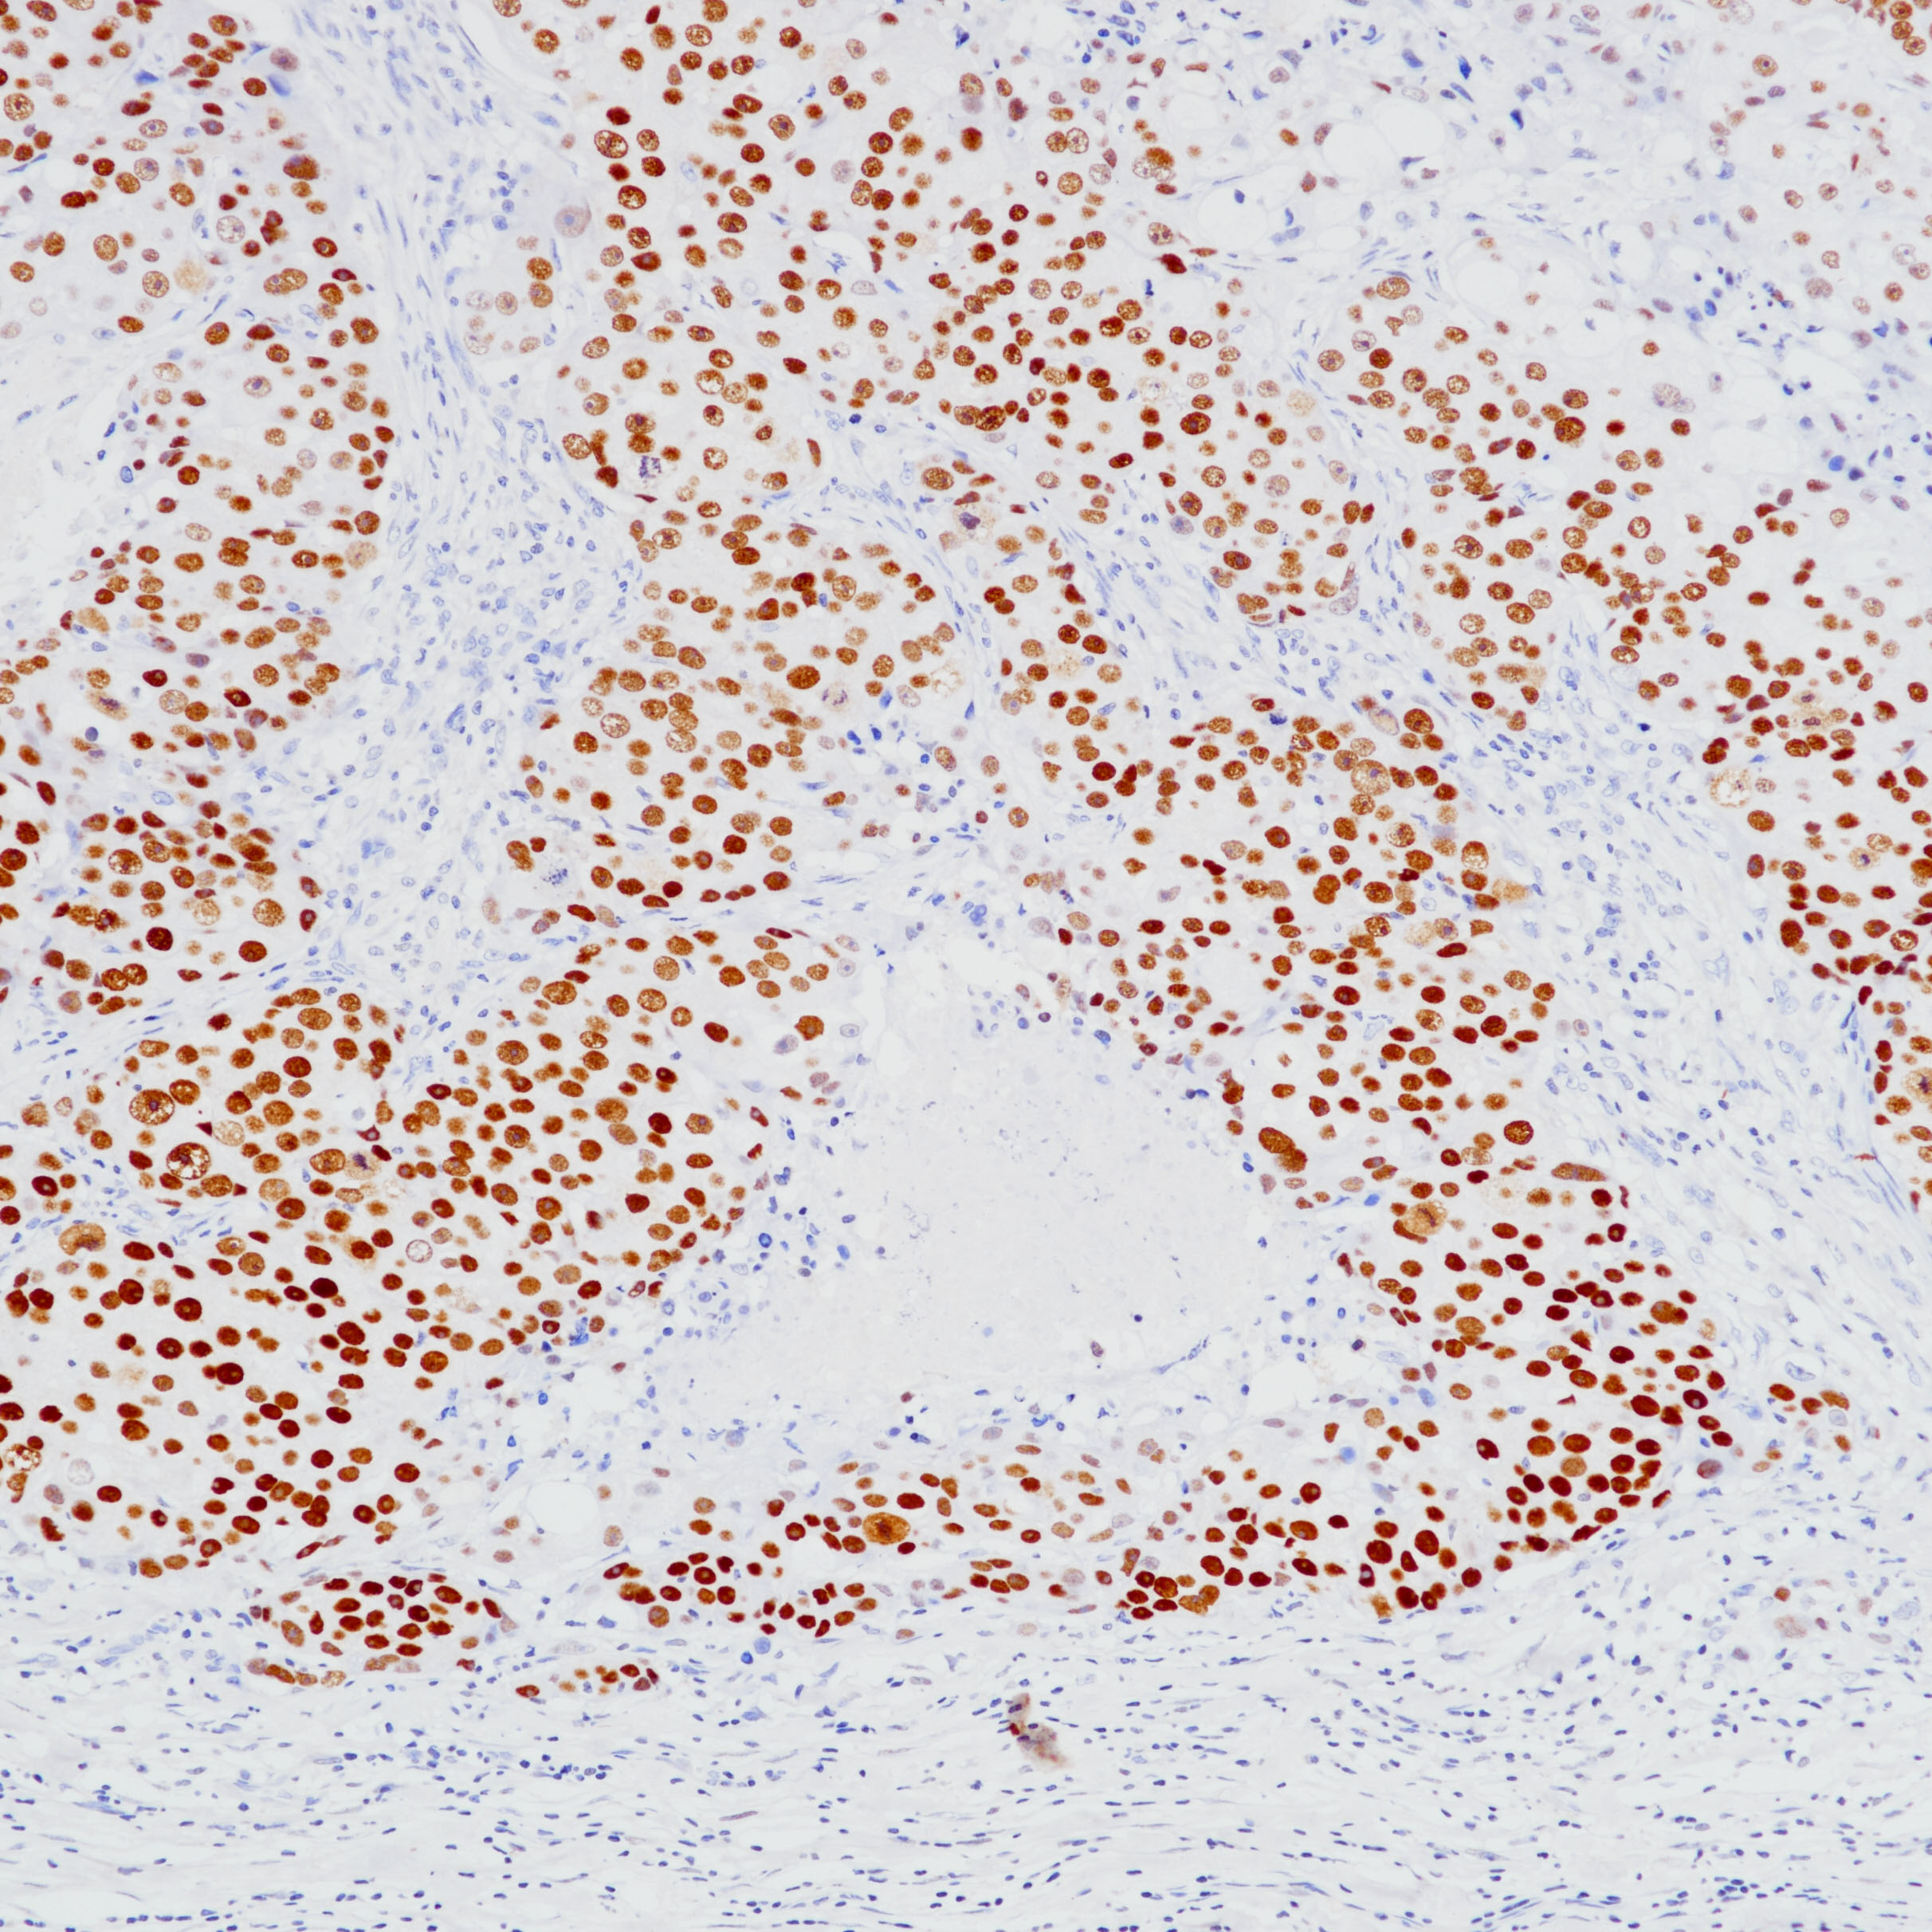

2.Wang J, Wang WL, Sun H, Huo L, Wu Y, Chen H, Gan Q, Meis JM, Maloney N, Lazar AJ, Yoon EC, Albarracin CT, Krishnamurthy S, Middleton LP, Resetkova E, Yu W, Tan D, Lu W, Solis Soto LM, Wang S, Wistuba II, Parwani AV, Prieto VG, Sahin AA, Li Z, Ding Q. Expression of TRPS1 in phyllodes tumor and sarcoma of the breast. Hum Pathol. 2022 Mar; 121:73-80.

3.Parkinson B, Chen W, Shen T, Parwani AV, Li Z. TRPS1 Expression in Breast Carcinomas: Focusing on Metaplastic Breast Carcinomas. Am J Surg Pathol. 2022 Mar 1;46(3):415-423.